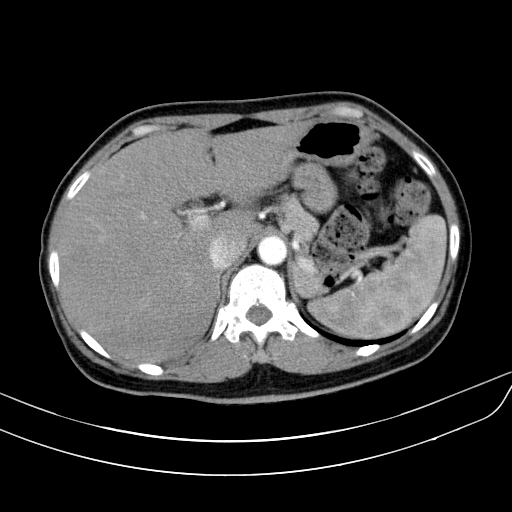

상복부통증을 주소로 내원한 50세 남자환자의 복부CT영상입니다. 담낭벽이 두꺼워져 있어 담낭염이 의심되어 치료하였으며, 조영증강 전 및 조영증강 후 영상에서 간 내에 별다른 국소병변은 보이지 않습니다.

왼쪽 영상이 arterial phase, 오른쪽 위는 portal phase, 마지막으로 오른쪽 아래 영상이 delayed phase 영상입니다. arterial phase에서도 어느정도 조영증강이 되어 주변의 간실질과 비슷한 감쇄도를 보이고 있습니다. 다만, portal 및 delayed phase에서 조영제가 완전히 빠져나가 뚜렷한 저음영으로 보이는 wash-out 양상을 보이지 않고 조영제가 병변 안에 어느정도 머물러 있습니다.